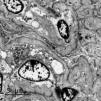

Internal medicina requested evaluation by nephrology due to deterioration of kidney function with a result of proteinuria of 8g in 24h. This way, taking of a renal biopsy is ordered, and is subjected to light microscopy, immunofluorescence and electron microscopy, with a report of podocyte lesion of 70% associated with glomerulosclerosis. focal and segmental (FSGS), severe acute tubular necrosis, interstitial fibrosis with moderate tubular atrophy and pigment casts. Thus, histochemistry was performed with a positive reaction for iron with evidence of intraluminal and cytoplasmic granular deposits in the proximal tubules compatible with hemosiderin and is negative for hemoglobin. During follow-up, she developed severe hyperkalemia refractory to medical management, requiring a single session of renal replacement therapy with hemodialysis. It was determined that the deterioration of renal function was evidenced by pigment cast nephropathy related to sickle cell disease.

In this particular case, the presence of pigment casts with a negative result for hemoglobin in immunohistochemistry was identified, which is why histochemistry was performed with positive staining for hemosiderin, indicating the presence of a pigment derived from hemoglobin. Pigment cast nephropathy was diagnosed, a condition in which renal function deteriorates due to the toxic effect of pigments containing the heme group. This condition can be caused by various causes, such as rhabdomyolysis (myoglobin pigment), cholestasis (bile acid pigment), and, as in this case, intravascular hemolysis (hemoglobin pigment). It is important to highlight that the presence of hemoglobin casts is rare, and what is described here is the accumulation of hemosiderin in the proximal tubule, as occurs in sickle cell crisis, where there are frequent and persistent episodes of hemoglobinuria.7,8 Furthermore, findings compatible with acute tubular necrosis (ATN) were observed in this patient. It is relevant to note that when ATN occurs alone, without cast nephropathy, special stains in immunohistochemistry do not detect hemoglobin and myoglobin, as happened in this case. It is important to keep in mind that, in case series of patients with pigment cast nephropathy, 100% of cases present acute tubular injury.9–11

Differential diagnoses such as light chain nephropathy should be considered when positivity for hemoglobin and myoglobin is not found. However, this diagnosis is ruled out due to the absence of light chain restriction on immunofluorescence. When there is lysis of red blood cells, excess hemoglobin is released. Under these circumstances, it is impossible for haptoglobin to capture all the hemoglobin that is filtered by the kidneys and absorbed by the tubular cells. At the intracellular level, iron cannot be processed and the excess accumulates as hemosiderin. This increase in free hemoglobin and hemosiderin is observed in conditions where there is continuous hemolysis, as in the case of paroxysmal nocturnal hemoglobinuria, complications of cardiac valve prostheses and, as presented in this case, in patients with sickle cell disease during crises of intravascular hemolysis.9,12

Iron deposition secondary to excessive hemolysis can cause kidney damage through three different mechanisms. First is direct iron toxicity, which leads to acute tubular injury. This process involves the stimulation of lipid peroxidation, the formation of free radicals that generate damage to cell membranes, the denaturation of proteins, the alteration of some enzymes related to glycolysis, affectation of mitochondrial and cytoskeleton integrity, induction of pathways of pro-inflammatory signaling, increased release of cytokines and chemokines through the NLRP3 inflammasome pathway. Likewise, it can incite cell death through caspases and cathepsins, and promote the development of CKD.9,13-15